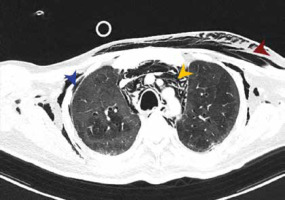

FIGURE 2

Image shows right-sided pneumothorax in a 22-year-old male patient on day 4 of ICU stay. He underwent intercostal drain insertion and had a favourable outcome